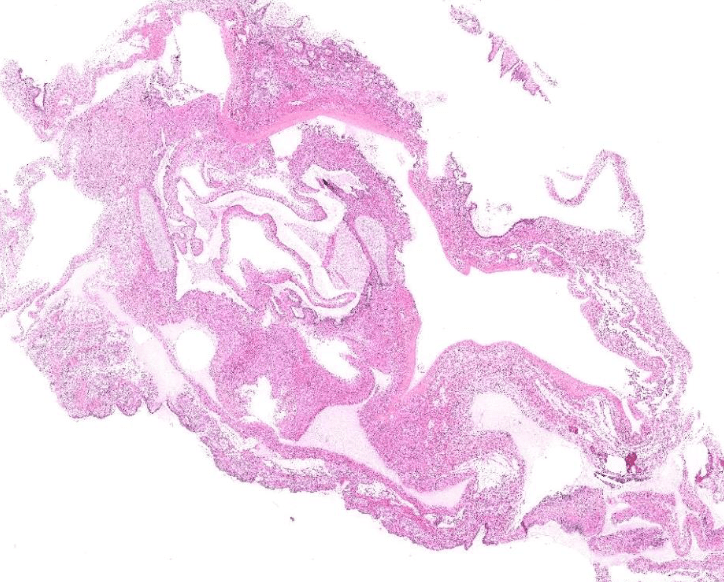

lung adenocarcinoma

colon cancer

endometrial cancer